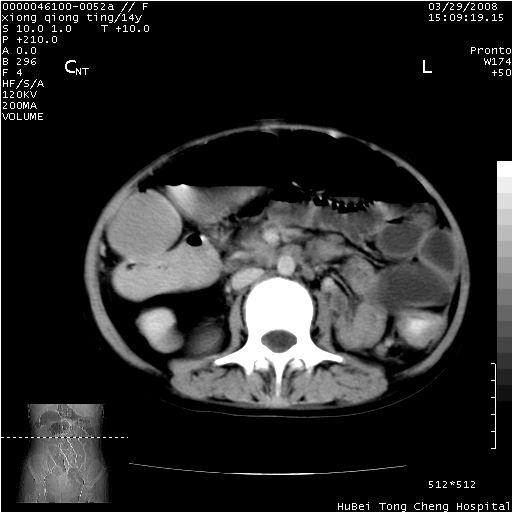

中下腹及盆腔ct轴位平扫+增强扫描(层厚10mm,螺距1.0,重建间隔10mm),图像如下:

(注:患儿检查当日上午9时口服胃肠道对比剂,下午3时许行ct扫描检查,未行对比剂直肠保留灌肠,检查当日患儿腹泻)

中下腹及盆腔ct轴位扫描(ps+ce)提示:腹部肠管明显充气扩张,并见数个不同宽度之气液平面;疑不全性肠梗阻或肠郁张。临床会诊考虑为患儿腹泻,肠郁张所致;后来未经特殊处理,患儿大便恢复正常,亦无腹胀。